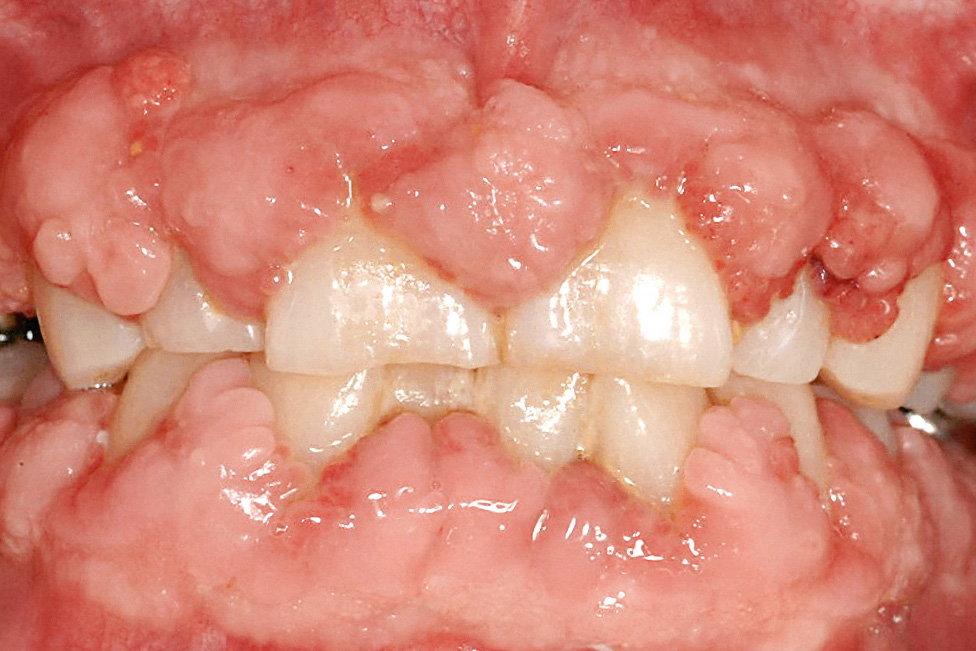

WirkstoffPräparat (Beispiele)Prävalenz von GingivawucherungenImmunsuppressivaCyclosporineSandimmun, NeoralErwachsene 25–30 % Kinder > 70 %AntikonvulsivaPhenytoinEpanutin, Phenhydan50 %7CarbamazepineTegretalnicht beschriebenVigabatrinSabrilseltenPhenobarbitalLuminal< 5 %ValproinsäureConvulexseltenKalziumkanalblockerNifedipinAdalat, Aprical, Corinfar, Duranifin24 %8–44 %9DiltiazemDilsal, Dilta, Corazet5–20 %VerapamilAzupamil, Cordichin, Falicard, Isoptin, Vera< 5 %10FelodipinFelobet, Felocor, MunobalseltenAmlodipinNorvascselten11IsradipinLomir, Vacsalnicht beschriebenNach Beginn der medikamentösen Therapie kommt es bevorzugt im Bereich der Papillen zu einer generalisierten oder lokalisierten Dickenzunahme der Gingiva12. Dabei ist die Prävalenz der Veränderung bei Kindern und Jugendlichen meist höher als bei Erwachsenen. Durch die Vergrößerung entstehen Pseudotaschen, die von den Patienten kaum zu reinigen sind. Die primär fibröse Wucherung kann dadurch sekundär entzündlich überlagert und deutlich verstärkt werden. Die Patienten fühlen sich meist nicht nur in ihrer Ästhetik beeinträchtigt, sondern es kann auch zu Problemen beim Essen, Sprechen und bei Kindern im Rahmen des Zahndurchbruchs kommen. Durch den Druck des wuchernden Gewebes können sogar Zahnstellungsänderungen hervorgerufen werden, die nach einer erfolgreichen Therapie reversibel sind.

Gingivawucherungen treten mit einer Häufigkeit von etwa 25 bis 30 % auf6 und manifestieren sich meist innerhalb von 3 Monaten nach Beginn der medikamentösen Behandlung (Maximum nach 6 Monaten; Abb. 3).

Abb. 3 Cyclosporin-A-induzierte Gingivawucherung bei einem Patienten nach Nierentransplantation.

Da es nach Nierentransplantation zu einer Erhöhung des Bluthochdrucks (renal verstärkt) kommen kann, werden den Patienten häufig Kalziumkanalblocker verordnet. Dadurch verstärkt sich der Effekt der beiden Medikamente, und die Häufigkeit von Gingivawucherungen nimmt zu.

Das Auftreten und das Ausmaß der Gingivawucherungen wird von mehreren Kofaktoren beeinflusst. Neben dem Alter der Patienten, der Dosierung und Dauer der Medikation spielt vor allem die individuelle Plaquekontrolle bzw. das Ausmaß der gingivalen Entzündung eine entscheidende Rolle.

Antikonvulsiva

Von verschiedenen Stoffen, die zur Therapie von Epilepsie eingesetzt werden, beeinflusst nur Phenytoin (Diphenylhydantoin) das parodontale Gewebe direkt. Daneben kommt Phenytoin auch bei der Behandlung bestimmter Herzrhythmusstörungen zur Anwendung. Die klinische Symptomatik tritt bei etwa 50 % der Patienten auf7. Es scheint keinen Zusammenhang zwischen der phenytoininduzierten Gingvaverdickung und dem Alter, der ethnischen Herkunft oder dem Geschlecht der Patienten zu geben. Wie bei Cyclosporin beginnt die Wucherung meist 3 Monate nach Beginn der Medikamenteneinnahme und ist im ersten Jahr der Behandlung am stärksten. Die ersten Zeichen der Gingivaverdickung treten im Bereich der Interdentalpapillen auf, die oft eine gestippelte Oberfläche aufweisen; bei lang andauernder Medikation kann das Gewebe die klinischen Kronen der Zähne bedecken (Abb. 4). Phenytoininduzierte Gewebewucherungen sind bei zahnlosen Patienten selten. Untersuchungen haben eine positive Korrelation zwischen dem Ausmaß der Wucherung, dem Entzündungsgrad, den Taschentiefen sowie der Prävalenz von weichen und harten Belägen gezeigt. Allerdings kann allein durch eine effektive Plaquekontrolle die Wucherung nicht vollständig eliminiert werden.